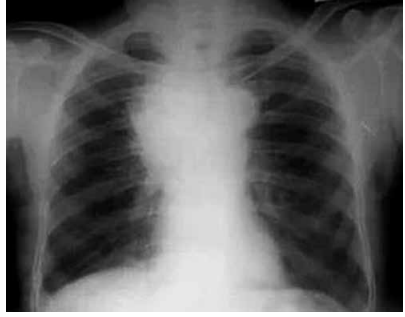

Paciente com 67 anos, tabagista, procura atendimento

em unidade de pronto atendimento. Relata dor precordial e nas costas, há quatro meses, inicialmente de leve

intensidade, mas que está piorando, além de fraqueza

nos membros inferiores e desconforto para engolir. Há

três dias, percebeu inchaço no pescoço, dos dois lados.

Exame físico: hemodinamicamente estável, pletora facial

moderada, edema supraclavicular bilateral, circulação

colateral na metade superior do tórax.

Radiografia de tórax a seguir:

(Arquivo pessoal; imagem usada com autorização)

O quadro clínico apresentado permite a elaboração de hipótese diagnóstica e de possível conduta, que devem ser, respectivamente: